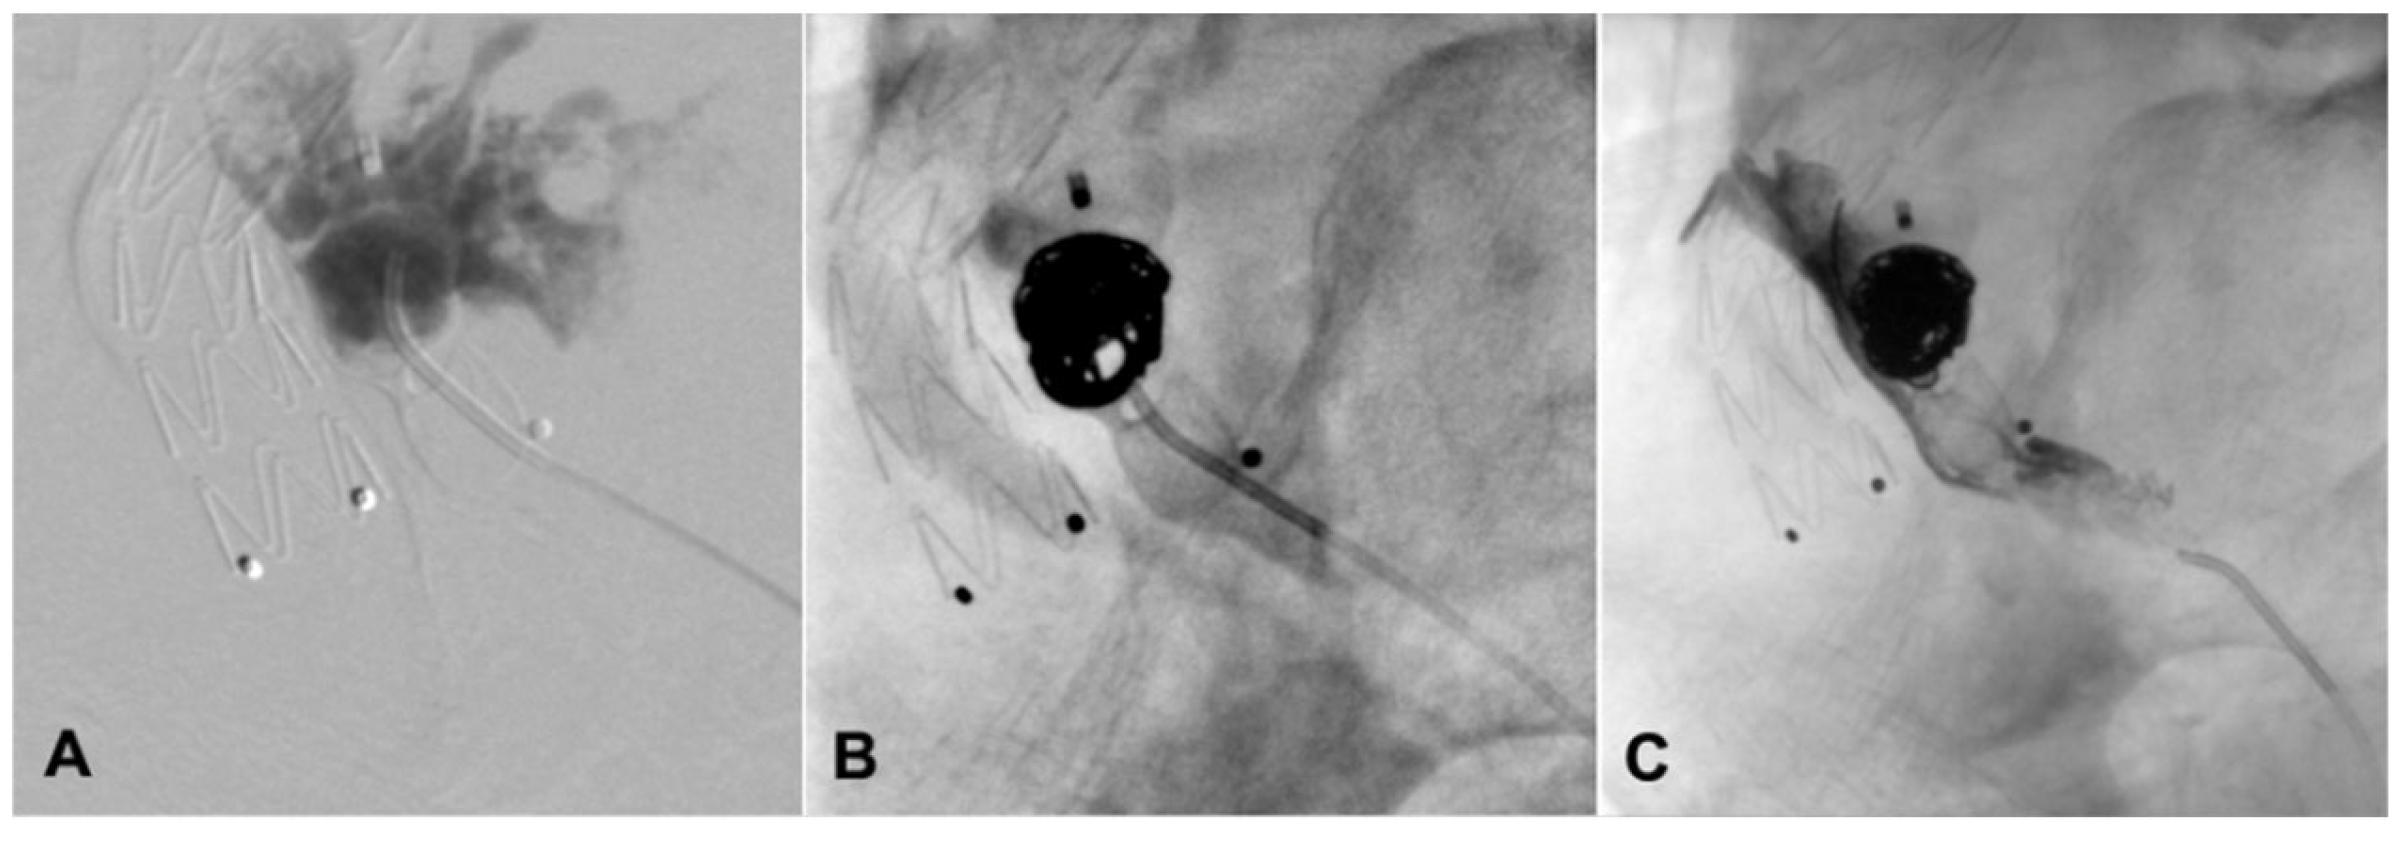

| Present case | Angiographic + DUS guided, 18G needle, sheathless |

Sac embolization with coils and liquid embolic agent | Manual compression | None | 12-months CT-scan, stable sac |